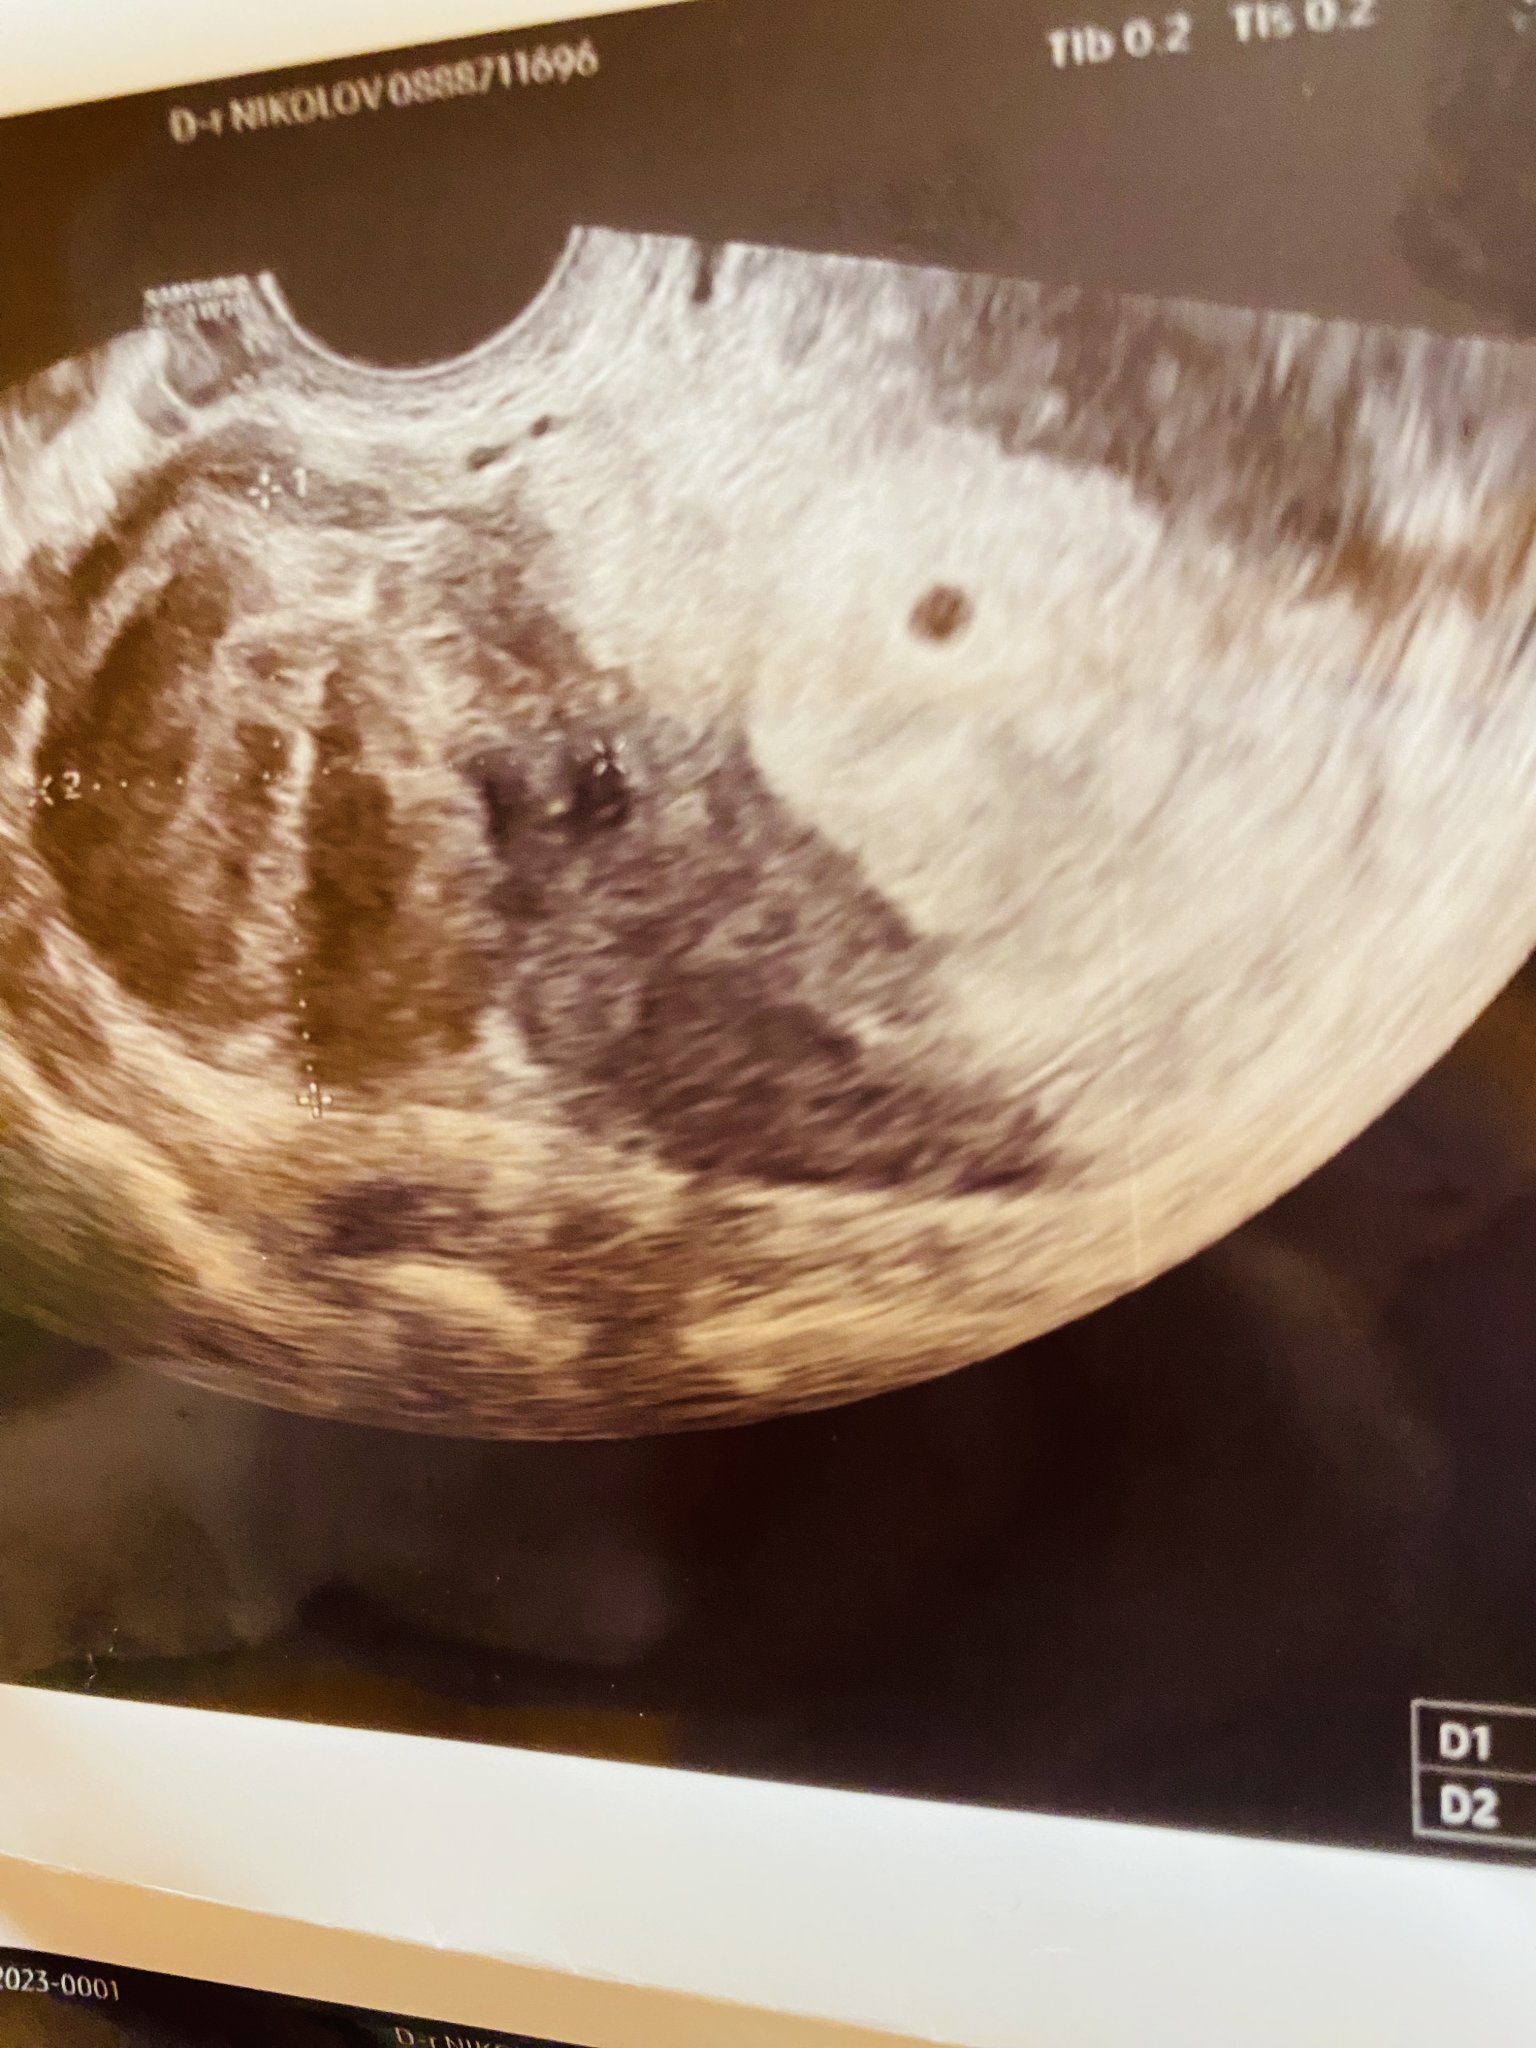

Кога е подходящо да се направи първият преглед при бременност?

Какви са някои препоръки за първия преглед по време на бременност?